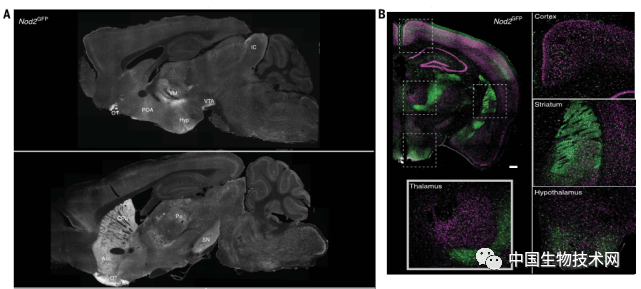

在该研究中,通过使用脑成像技术,研究人员最初观察到小鼠的NOD2受体由大脑不同区域的神经元表达,特别是在

下丘脑

区域。

众所周知,下丘脑管理着诸如体温、生殖、饥饿和口渴等重要功能。